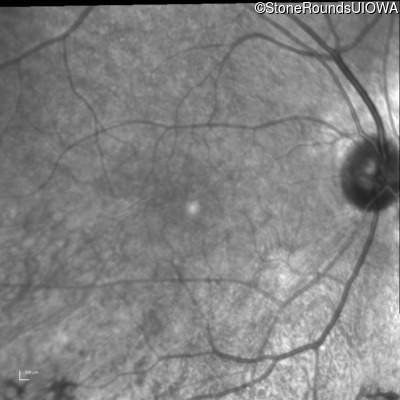

Infrared Fundus Photograph - Right - 20/16

Exemplar

Infrared Fundus Photograph - Left - 20/25